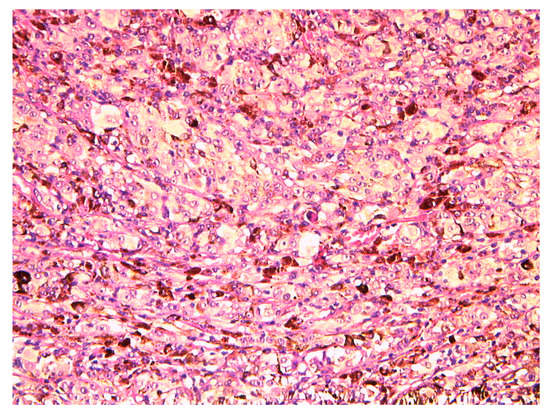

Case Presentation